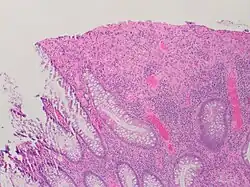

Micrograph showing intestinal crypt branching, a histopathological finding of chronic colitis. H&E stain.